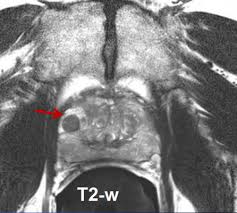

The Importance Of Mri S In Diagnosing Prostate Cancer Rosetta Radiology

The Importance Of Mri S In Diagnosing Prostate Cancer Rosetta Radiology from rosettaradiology.com

15.09.2021 · mri a valuable tool in early diagnosis and evaluation of the extent of tumors, such as prostate cancer. 20.02.2002 · in prostate cancer patients, mri may be used to examine the prostate and nearby lymph nodes to distinguish between benign (noncancerous) and malignant (cancerous) … Mr imaging for diagnosis and staging of prostate cancer has clinically available and used by several centers for many years. Mri can not only confirm the presence of prostate cancer but pinpoint its location. The current diagnostic pathway for prostate cancer has resulted in overdiagnosis and consequent overtreatment as well as underdiagnosis and missed diagnoses in many … If prostate cancer has been found, mri can be done to help determine the extent (stage) of the cancer. Mri is valuable in diagnosing many conditions … In its history it has undergone …